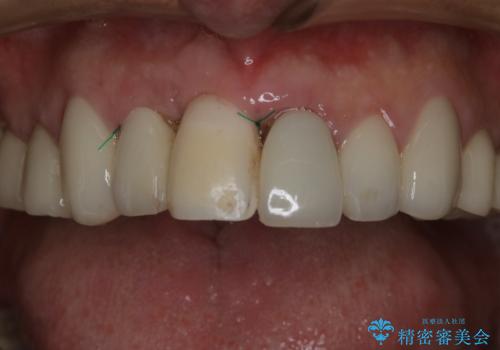

それと比較すると、今回の方法では骨にしっかりと固定されているインプラントに単独で仮歯を装着することができるためフロスも通せますし、ある程度負荷のかかる食事も気にせずできるようになります。

患者様のご要望もあり、審美性の確保ができる抜歯早期埋入→埋入後即時荷重という手術法を取りました。